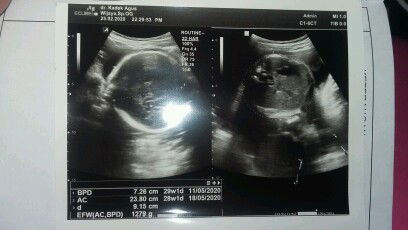

Assalamualaikum bunda saya mau cerita tentang kehamilan saya sampai saya lahiran dn alhamdulillah sekarang dedek sdh berumur 7 bulan sdh bisa duduk tapi blm bisa merangkak masi belajr.begini awalnya Saya tau hamil baby twins pas uk 12week bun,muntah parah sampai 2 Kali masuk RS Alhamdulillah Saya lalui walau Saya setiap mual harus minum obat mual sampai usia kandungan 7bulan memang punya keturun kembar bun dari keluarga ibu Saya.selama hamil Saya cuma 3 Kali USG usia 12week 28week sama 36weeek Waktu 28week alhamdulillah kelaminnya ternyata cowok2.hpl 1 mei 2020 Tapi sidedek lahir 16 April 2020 SC krn ketuban rembes bun yg Buat Saya sedih anak 1.Saya bbnya 1,3 2. 2,1 Setelah oprasi selesai Saya Dan baby boy no 2 bisa d bawa ke kamr inap sedangkan baby boy pertama Saya masuk incubator sedihh tangis Dan doa yg Saya lakukan tapi sayang baby boy Saya yg no 1 hanya bertahan 4 hari karna gula darah rendah kena penyakit kuning Dan sesak.. tangis pilu rasanya dunia ini gelap Ionian Saya punya baby kembar ternyata cuma mimpi padahal dri usia kandungan 7 bulan Saya sdh nyiapin barang Buat dedek semua dua karna Saya tw kalau Saya hamil kembar. Terpukul tapi Saya cuma bisa iklas Tinggal 1 baby boy Saya yg Saya syg

Semalem habis USG alhamdulillah di kasi baby kembar cowok cowok usia kandungan 30 week5d Bertanya 1.6 &1.3 Kok beda beda ya bun Saya takut prematur Berat janin segitu normal gak????